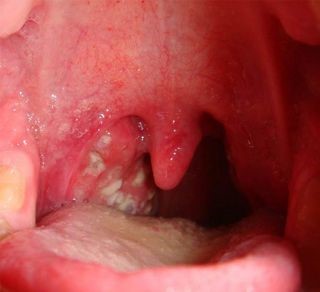

Образующаяся слизь может быть прозрачной, если ее причиной стал вирус, или иметь желто-зеленый цвет, если инфекция бактериальная. При осмотре горла видно, что задняя стенка воспалена, возможен небольшой отек. Могут быть признаки воспаления миндалин, признаки бронхита, трахеита или пневмонии. Бронхиальная астма тоже может стать причиной присутствия мокроты в горле. При проблемах в бронхах или легких образующийся в большом количестве секрет поднимается вверх и скапливается в горле.